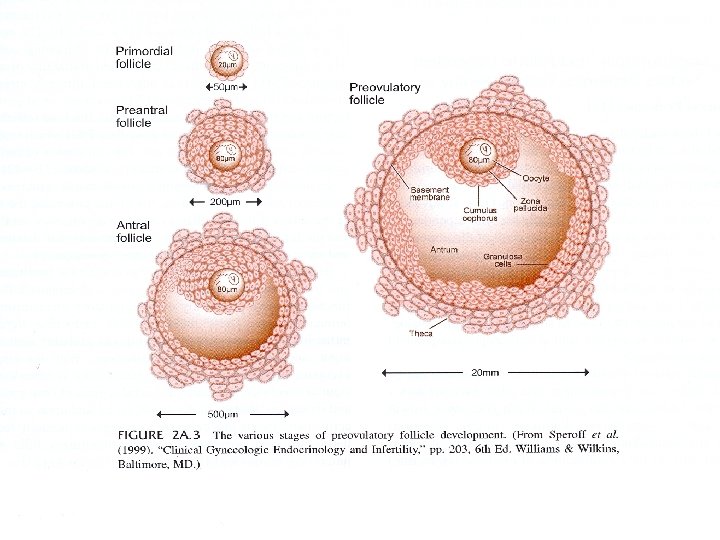

Follicular Maturation FSH • Induces early growth • Controls follicle number LH • Provides estrogen precursors • Needed for latter stages of growth

Erken Foliküler Faz Thecal cell LH Androstenedione Testosterone Granulosa cell FSH IGF II Aromatisation E 1 E 2